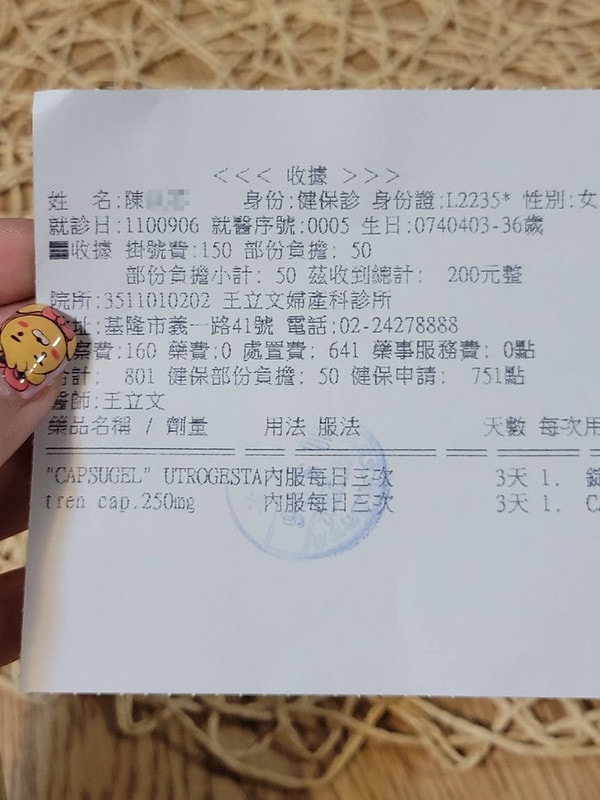

產檢的婦產科診所是:王立文婦產科診所

關於安胎藥

那時候拿到的藥長這樣

至於為什麼會出血,有滿多種原因的

醫生是說我有胎盤位置過低的問題